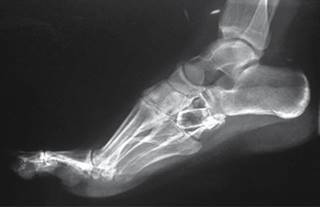

En las radiografías dorsoplantar y lateral de pie derecho se observa injerto óseo en el centro de una lesión en cuboides, radiotransparente, heterogénea, multilobulada, con bordes irregulares que sobrepasan la cortical lateral, multilobulados (Figuras 2 y 3).

Figura 3: Radiografía lateral de pie.